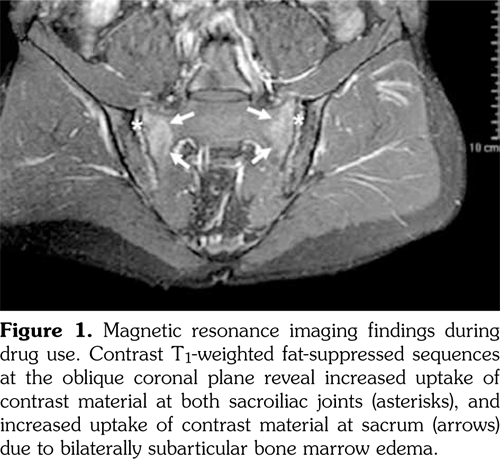

Physical examination revealed limited and painful lumbar movements in all directions. Modified Schober’s test was measured as 19 cm, while fingertip to floor distance was measured as 5 cm. There was full range of motion in hip joint, however, hip movements were painful. Chest expansion, sacroiliac provocation tests (mennel, gaenslen), and neurological examination findings were normal. Tinnel’s sign and Phalen’s maneuver were negative. Thus, the underlying origin of the back pain was considered to be inflammatory, and laboratory tests were performed. Laboratory analysis demonstrated normal biochemical values and complete blood count. Acute phase reactants including C-reactive protein and erythrocyte sedimentation rate were 3 mg/L (normal range: 0-3 mg/L) and 1 mm/h (0-15 mm/h), respectively. Urinalysis was normal. Serum vitamin B 12 and folic acid levels, thyroid function tests, and parathyroid hormone levels were within normal range. Hepatitis panel, including hepatitis B surface antigens, hepatitis B surface antibodies, hepatitis C virus antibodies, and human immunodeficiency virus antibodies, was negative. Serological evaluations including anti-cyclic citrullinated peptide and anti-nuclear antibody tests were negative. In addition, rheumatoid factor test was also negative. Spinal magnetic resonance imaging (MRI) was considered to be normal. However, sacroiliac MRI showed bilateral bone marrow edema and subchondral sclerosis (Figure 1 and Figure 2). Nerve conduction studies and electromyography revealed sensorimotor demyelinating polyneuropathy (Table 1 and Table 2).

Acne fulminans is a component of SAPHO syndrome (acronym for Synovitis, Acne, Pustulosis, Hyperostosis and Osteitis). In SAPHO syndrome, constitutional symptoms, abnormal laboratory findings and musculoskeletal symptoms are observed as well as necrotizing acne. Sacroiliitis was detected in 21% of the patients having acne fulminans in association with arthritis. In addition, development of sacroiliitis after systemic isotretinoin treatment was also reported in patients with SAPHO syndrome.(15,16) Dinçer et al.(17) reported sacroiliitis development in three patients aged 18-25 years who used 15-25 mg/day isotretinoin for a time period ranging from three months to two years. Unilateral sacroiliitis developed in patients who used isotretinoin for three months while bilateral sacroiliitis developed in patients who used isotretinoin for two years. Human leukocyte antigen B27 (HLA-B27) positivity was detected in one of three cases. Ekşioğlu et al.(3) also reported bilateral sacroiliitis and demyelinating polyneuropathy in a patient 20 years old, who used isotretinoin for three months (30 mg/day during first two months and 40 mg/day during last month). HLA-B27 positivity was detected in this case. Our patient was 25 years old and used isotretinoin for six months (20 mg/day during first three months and 40 mg/ day during last three months). Sacroiliitis developed bilaterally in our case. Sacroiliitis in our case was linked to isotretinoin use, as the patient had no musculoskeletal complaint prior to isotretinoin use. Furthermore, hip pain, back pain and active sacroiliitis findings on MRI emerged three months after prescription of isotretinoin. Complaints and active sacroiliitis findings on MRI disappeared two months after withdrawal from drug.